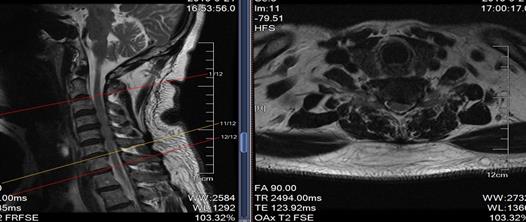

这是一例胸7-8间盘突出的患者,患者下肢无力越来越重,已经到了不能走路的地步,必须手术才能解决,可是胸椎手术风险比腰椎大的多,是真有可能瘫痪的,我们顶住压力,为了患者的健康着想,为他做了脊柱内镜下胸椎间盘摘除术。

手术很顺利,间盘摘除的很彻底,患者终于又可以站起来走路了。

来自大连的张大爷(化名)备受颈椎病的折磨,左上肢麻木疼痛难忍,去过好几家医院都说让开放手术,张大爷很恐惧,经多方打听了解到我们医院能做微创手术就来我院就诊,我们给他做了颈椎椎间孔镜手术。

术后患者症状明显减轻,张大爷终于可以睡个好觉了。